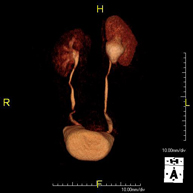

Prova diagnòstica no invasiva que consisteix en l'obtenció d'imatges d'alta definició anatòmica del fetge mitjançant l'ús d'un camp electromagnètic i ones de ràdio (amb un emissor i un receptor). No utilitza radiació ionitzant. Es realitza per estudiar qualsevol lesió localitzada en el fetge. Normalment es requereix l'ús de contrast paramagnètic (Gadolini) per caracteritzar les lesions. És necessari realitzat la prova en dejú (6 hores). - RM de Ronyons

Prova diagnòstica no invasiva que consisteix en l'obtenció d'imatges d'alta definició anatòmica d'ambdós ronyons mitjançant l'ús d'un camp electromagnètic i ones de ràdio (amb un emissor i un receptor). No utilitza radiació ionitzant. Es realitza per estudiar qualsevol lesió localitzada en ambdós ronyons. Normalment es requereix l'ús de contrast paramagnètic (Gadolini) per caracteritzar les lesions. - RM Glándulas Suprarrenales

- URO-RM

Prueba diagnóstica no invasiva que consiste en la obtención de imágenes de alta definición anatómica del sistema urinario mediante el empleo de un campo electromagnético y ondas de radio (con un emisor y un receptor). No utiliza radiación ionizante. Requiere el uso de contraste paramagnético (Gadolinio) que se excretará por el sistema urinario y nos permitirá obtener imágenes en 2D y 3D. - RM Próstata

Prueba diagnóstica no invasiva que consiste en el estudio de las arterias renales, obteniendo imágenes de alta definición anatómica mediante el empleo de un campo electromagnético y ondas de radio (con un emisor y un receptor). Es indispensable el uso de contraste paramagnético (Gadolinio). Sin embargo, no utiliza radiación ionizante. La calidad de las imágenes permite realizar reconstrucciones en 2D y 3D. Esta prueba está indicada por ejemplo en aquellos pacientes que sufren de HTA refractaria al tratamiento, en pacientes con lesiones renales para tener un mapa "vascular" pre-quirúrgico, etc. - Entero-RM